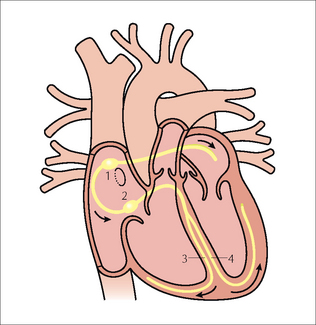

image

Figure 12.7 Optimal electrode position. Single chamber pacemaker. The ventricular lead has its tip situated at the apex of the right ventricle. (Retouched.)